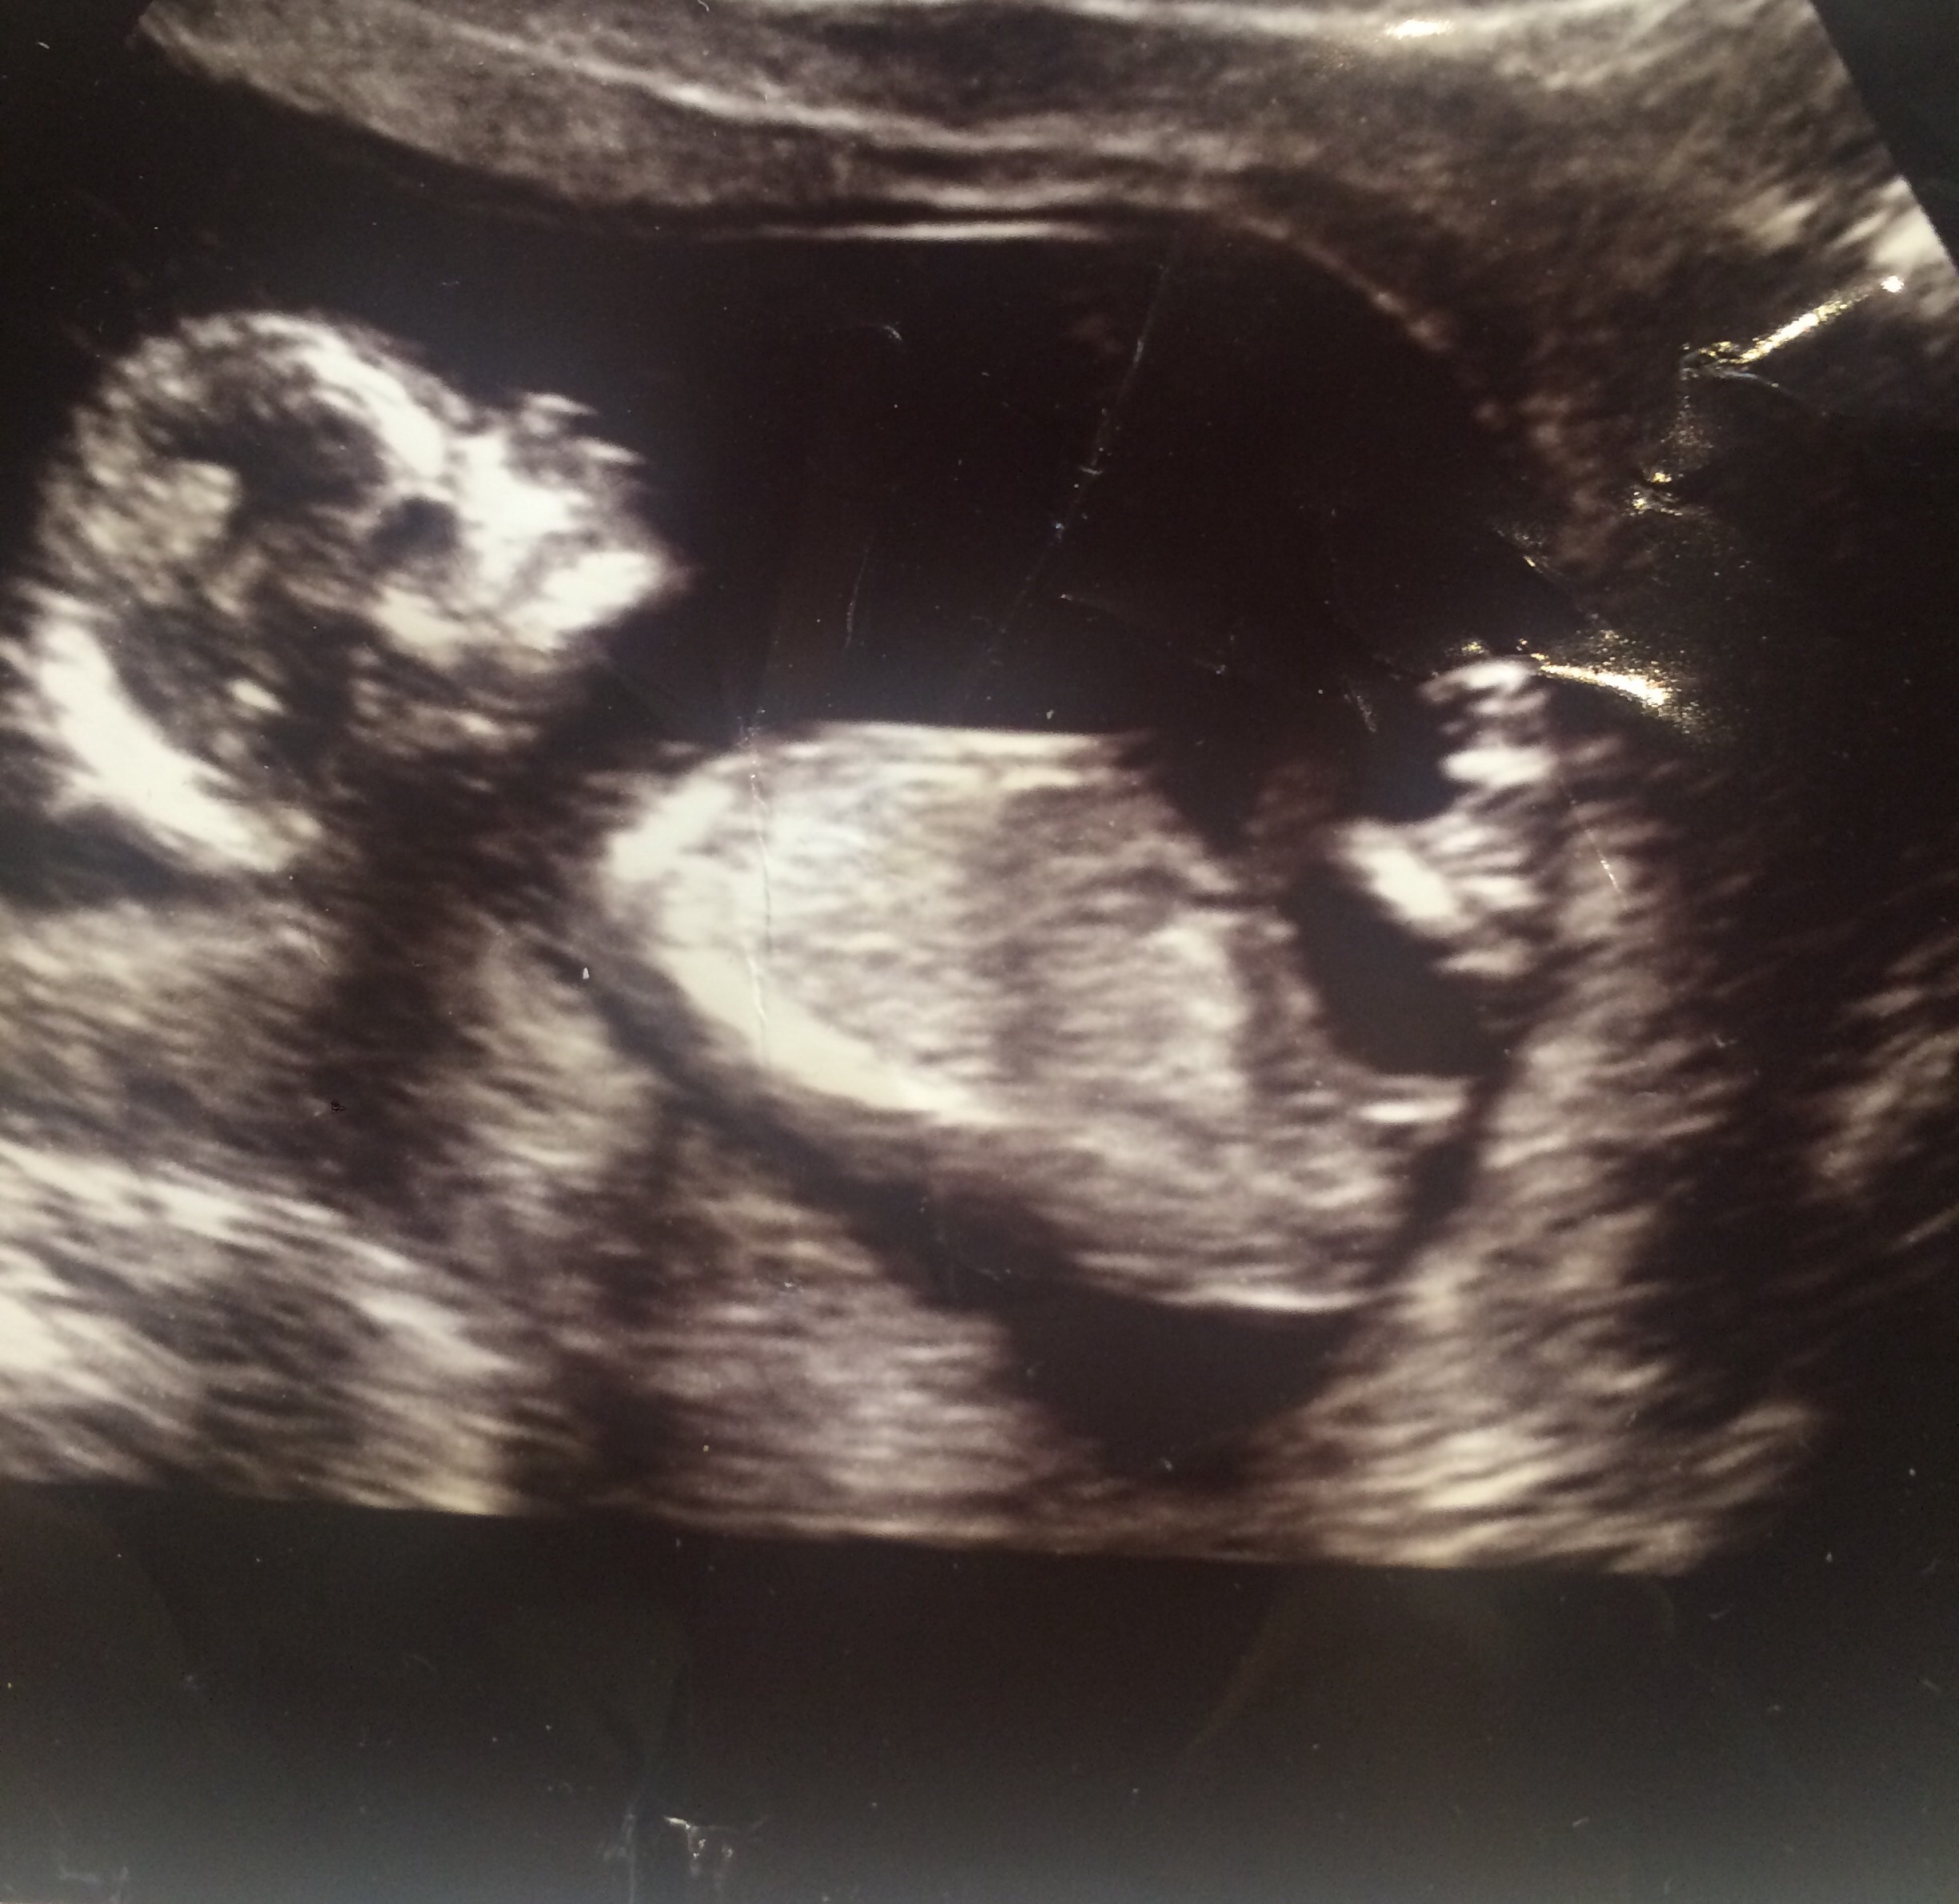

Finding out next week :) what does everyone think? Attachment 37723

Girl!

You were right! It is a little girl! :)